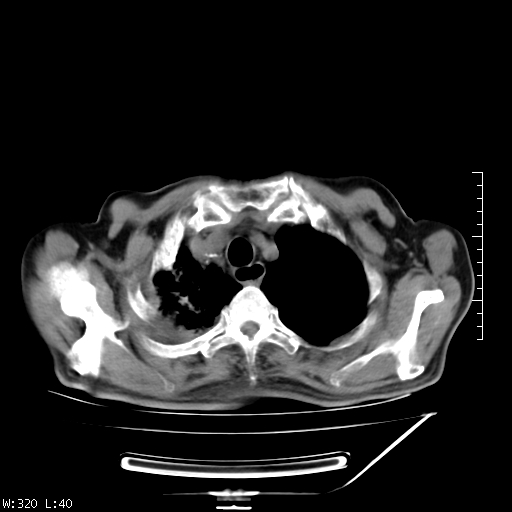

标题: CT23994:男、72、咳嗽、气短两月余,近来消瘦。 [打印本页]

标题: CT23994:男、72、咳嗽、气短两月余,近来消瘦。

右上肺实变,与胸膜关系密切,右肺容积缩小,隆突下淋巴结增大,考虑1 肺结核 2 肺癌

右上肺大片状密度增高影,与胸膜关系密切,内见低密度透亮影,胸膜下可见三角形不张影,左下肺沿支气管走形结节影,纵膈内淋巴结显示。考虑结核并疤痕性不张可能性大,建议穿刺活检,排除肺泡癌。